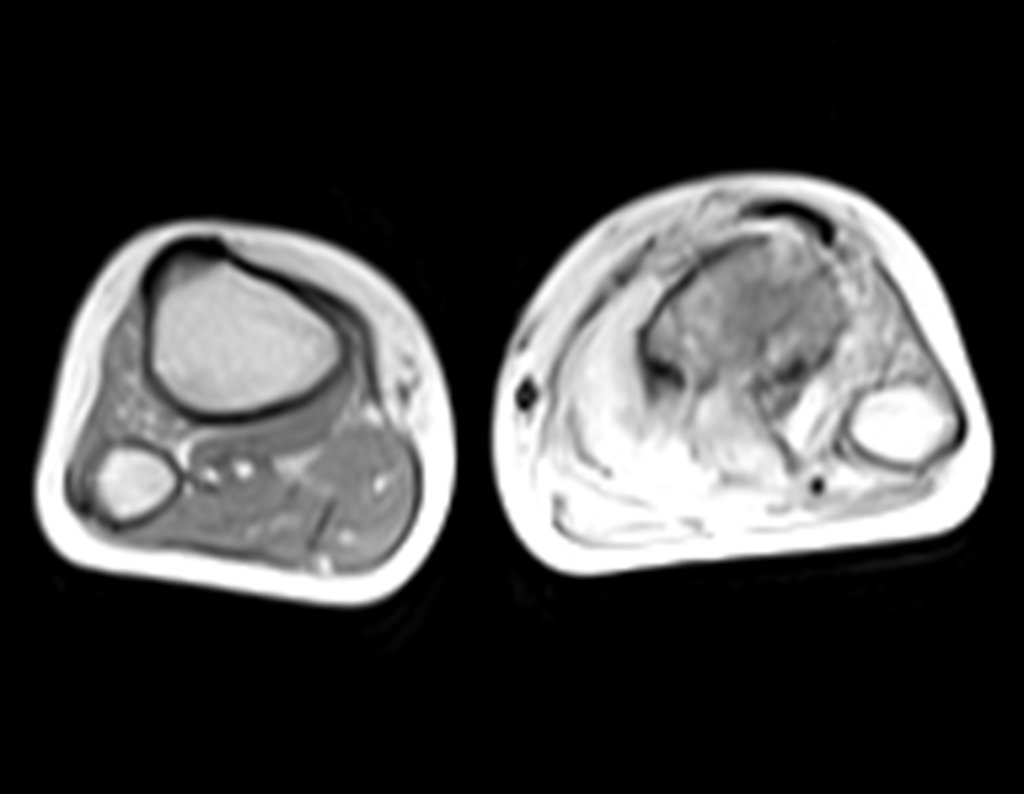

Ingresó en el hospital en mayo y se sometió a una biopsia por punción. El informe anatomopatológico indicó osteosarcoma central convencional localizado, con cultivos negativos. Se le realizó estadificación con TC de tórax, gammagrafía ósea de todo el cuerpo y resonancia magnética del miembro inferior derecho. Se le realizaron tres ciclos de quimioterapia neoadyuvante con Platino y Doxorrubicina, con buena respuesta.